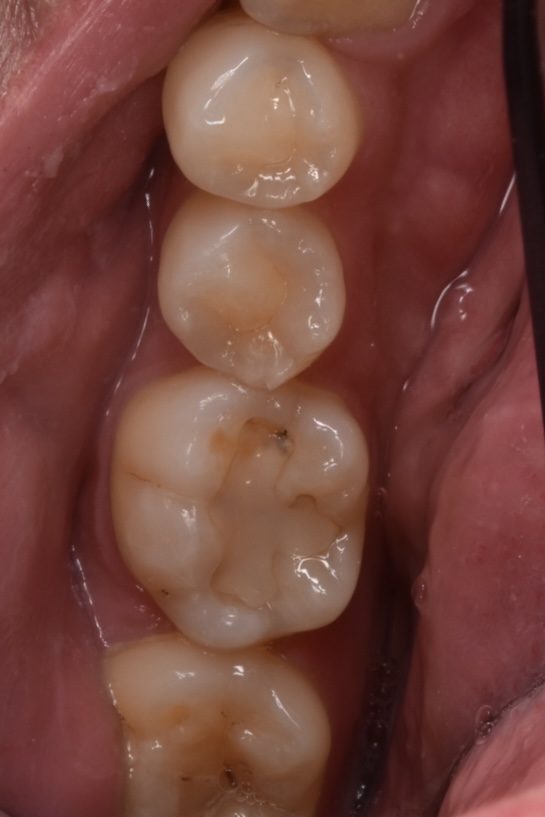

30代男性 ご夫婦で通院してくださっている方です。今回は以前保険治療で奥歯の虫歯治療をした歯の2次虫歯のため綺麗にしっかり治療したいとの事で、自由診療枠で治療させて頂ける事になりました。ダイレクトボンディングで治療するため、通院の必要はなく1回で終了です。

治療前と治療後

左下の第一大臼歯の治療です。何年も前の他院保険治療による虫歯治療の虫歯の再発です。レジンと歯の隙間が茶色でくっきりとわかります